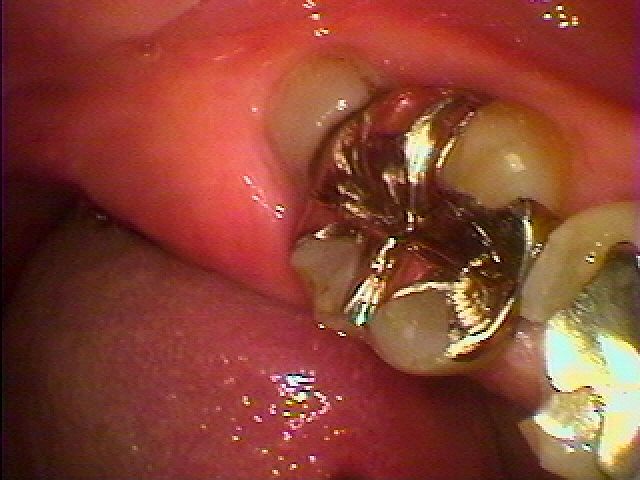

ブログ一覧|広島市安佐南区の歯科医院 ブログ一覧 トップ ブログ一覧 お知らせ スタッフブログ ブログ一覧 お知らせ 2019/09/10 左下親知らずの完全水平埋伏歯の難抜歯 分割抜歯 お知らせ 2019/09/09 左下の湾曲2根管の親知らずの抜歯 これも抜けにくい親知らずでした お知らせ 2019/09/09 右下親知らずの根湾曲 親知らずは大根のようでまれに根が曲がっていて抜けにくい親知らずも多々あります お知らせ 2019/09/07 術者、患者ともに大変な治療かと思います 下顎の吸着のある入れ歯はないため、安定をインプラントのように顎骨に求めれば安定は履かれますが、高齢者では負担も大きい治療の1つです お知らせ 2019/09/07 下前歯部はジルコニアブリッジ 欠損部はスマートデンチャーにてマネージしました お知らせ 2019/09/06 無歯顎の下前歯部のインプラント埋入 3本埋入 2本暫間インプラント埋入 お知らせ 2019/09/05 下の歯が動いて難しい 食べれるようにしてほしい 一度入れ歯を作成したが駄目で、インプラントにてパーシャルデンチャー予定 お知らせ 2019/09/05 ジルコニアブリッジ臨床 右上2番が割れて2か月前に抜歯 << 1 2 3 4 5 … 385 386 387 388 389 … 870 871 872 873 874 >> Web診療予約 初めての方へ 選ばれ続ける理由 院内設備について 歯が痛いしみる一般歯科 歯がぐらぐらする歯周病 健康な歯を保ちたい予防歯科 子供の虫歯予防をしたい小児歯科 銀歯をセラミックに審美歯科 白い歯を目指しませんか?ホワイトニング 矯正専門医がいるので安心矯正歯科 抜けた歯を補いたいインプラント・入れ歯 医院案内 スタッフ紹介 メリィハウス歯科クリニックオフィシャルホームページ ラベンダー歯科クリニックオフィシャルホームページ お知らせ・ブログ ホーム 診療科目 一般歯科 歯周病治療 予防治療 小児歯科 審美治療 ホワイトニング 矯正歯科 入れ歯・インプラント マウスピース矯正 初めての方へ 院長・スタッフ 設備紹介 医院案内・アクセス メニューを閉じる